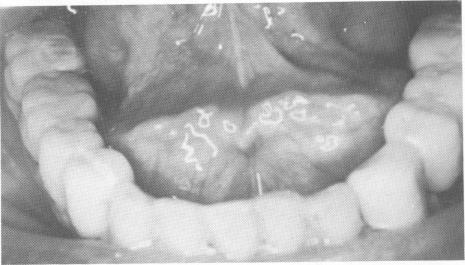

Fig. 15-48. Both lower partial dentures are also cemented into position.

2 Mandibular partial dentures are cemented into position